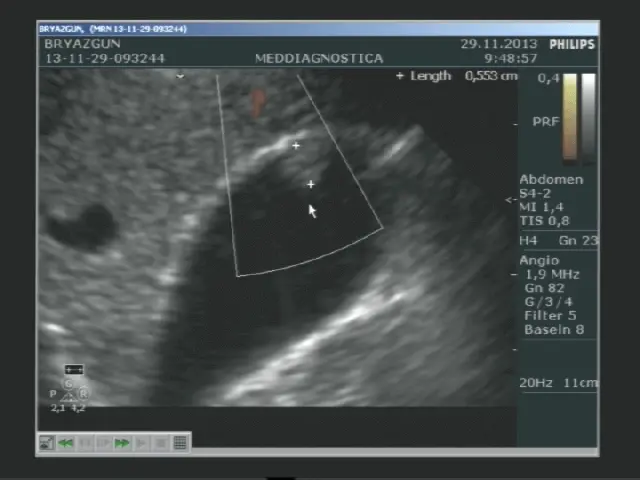

Тепер детальніше. Процедура – дивовижна річ. Як комп’ютерний відеосканер, тільки у реальному часі. Проте, з невеличкою різницею — нічого космічного. Лікар прикладає апарат до живота і бачить чорнобілі тіні. Такий собі мультик для дорослих, тільки без Popcorn.

Шляхом ультразвукових хвиль органи візуалізуються, даючи змогу виявити піщаду — хаваєм всі потенційні проблеми.